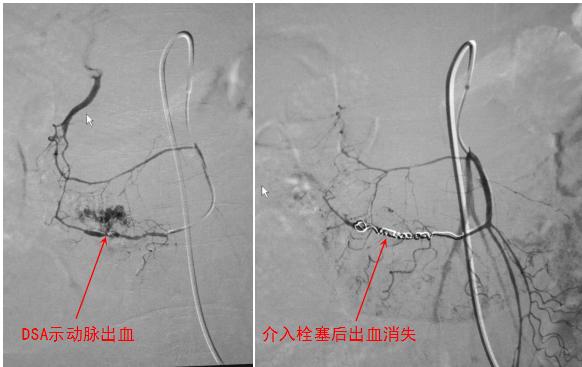

的确,介入医生采用血管造影的方式,可以很容易地筛查到出血的“责任血管”,有时还可以明确一些出血的原因如动脉瘤、动静脉畸形或胃肠道肿瘤等。明确诊断后,后续的介入治疗就简单了——栓塞“责任血管”,就可让出血立即停止!而有些病例(如肿瘤)经过介入止血后,由于最好是切除病灶,还可再交给外科医生接着处理——诊断明确了,出血部位弄清了,外科医生就可将病变轻松地“手到擒来”。

消化道出血栓塞前后对比